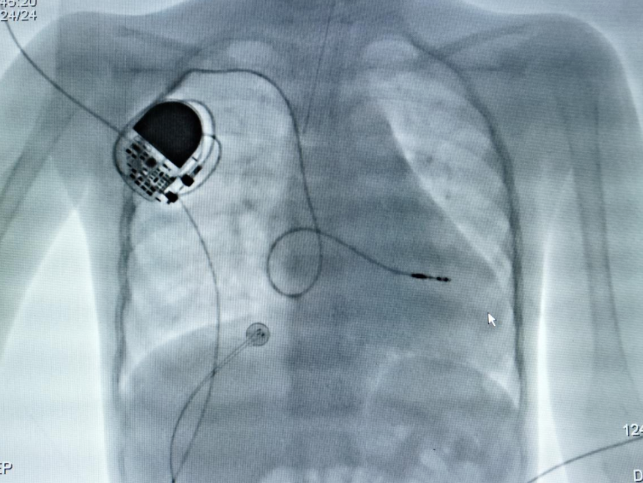

图片

术后影像